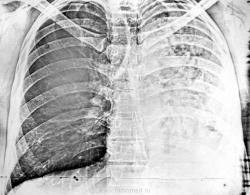

Не будучи специалистом в этой области, рискну предположить казеозную пневмонию левого лёгкого, а уменьшение объема пораженного легкого (смещение органов средостения) за счёт предсуществовавшего пневмофиброза, пример которого видим справа в верхней доле.

Я-бы рискнул предположить аномалию развития нижнедолевого бронха слева, возможно, и других бронхов слева, возможно даже с каким-то вариантным недоразвитием легочной ткани (уж очень средостение смещено влево), ну и возможно, с присоединением к этим аномалиям воспалительного процесса.

Тогда мною выставлен диагноз метатуберкулезного цирроза левого легкого, приехал конультант из облтубдиспансера и забрал пациента с собой немедленно и безоговорочно -что бывает редко... К сожалению судьбу не знаю. А в бронхах действительно вероятно что то было, но - в армии служил....

средостение и трахея смещены в пораженную сторону, а левый боковой не добавите?

Срединный срез

Я когда с этим больным разбирался, а были еще снимки, - отметил для себя, что все бронхи проходимы... А в архиве остались только эти два снимка...

Такая картина навевает мысль о врожденной патологии, осложненной воспалительным процессом. Какая-нибудь кистозная гипоплазия легкого?

Наверное это плевроцирроз.